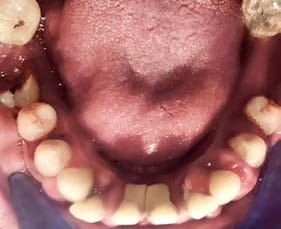

Corrección de mordida abierta anterior en paciente clase II con deglución atípica. Caso clínico

Corrección de mordida abierta anterior en paciente clase II con deglución atípica. Caso clínico.

Objetivo: presentar un caso clínico de paciente con mordida abierta anterior, clase II y deglución atípica tratada con aparatología fija ortodóntica.

Caso clínico: paciente femenino de 19 años, patrón dolicofacial, perfil convexo, clase II esqueletal debido a una retrusión mandibular, mordida abierta anterior esqueletal, clase II molar, clase canina no establecida por mordida abierta, apiñamiento severo superior e inferior y deglución atípica.

Resultados: obtención de una clase canina I y clase molar II funcional, se corrigieron las sobremordidas horizontal y vertical, y se logró la coincidencia de líneas medias facial y dental. El manejo de la mordida abierta anterior se llevó a cabo por medio de la corrección del hábito de deglución atípica con la ayuda de spikes de resina, elásticos intermaxilares y arcos utility, y se obtuvieron buenos resultados estéticos, dentales y funcionales.